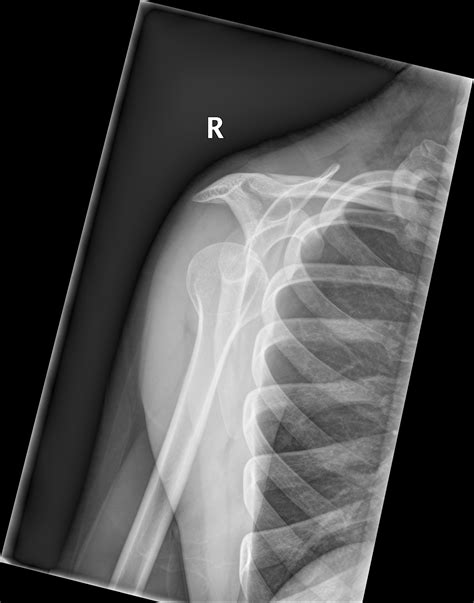

Diagnosis of Inferior Shoulder Dislocation

Diagnosing an inferior shoulder dislocation involves a combination of physical examination and imaging tests. The diagnostic process typically includes:

• Physical examination: A healthcare provider will assess the shoulder for deformity, swelling, and range of motion.

• X-rays: Imaging tests can confirm the dislocation and rule out fractures or other injuries.

• CT scan or MRI: These advanced imaging techniques may be used to evaluate the extent of the injury and plan treatment.

Accurate diagnosis is crucial for determining the appropriate course of treatment and ensuring a successful recovery.

• inferior shoulder dislocation xray

• inferior shoulder dislocation xr